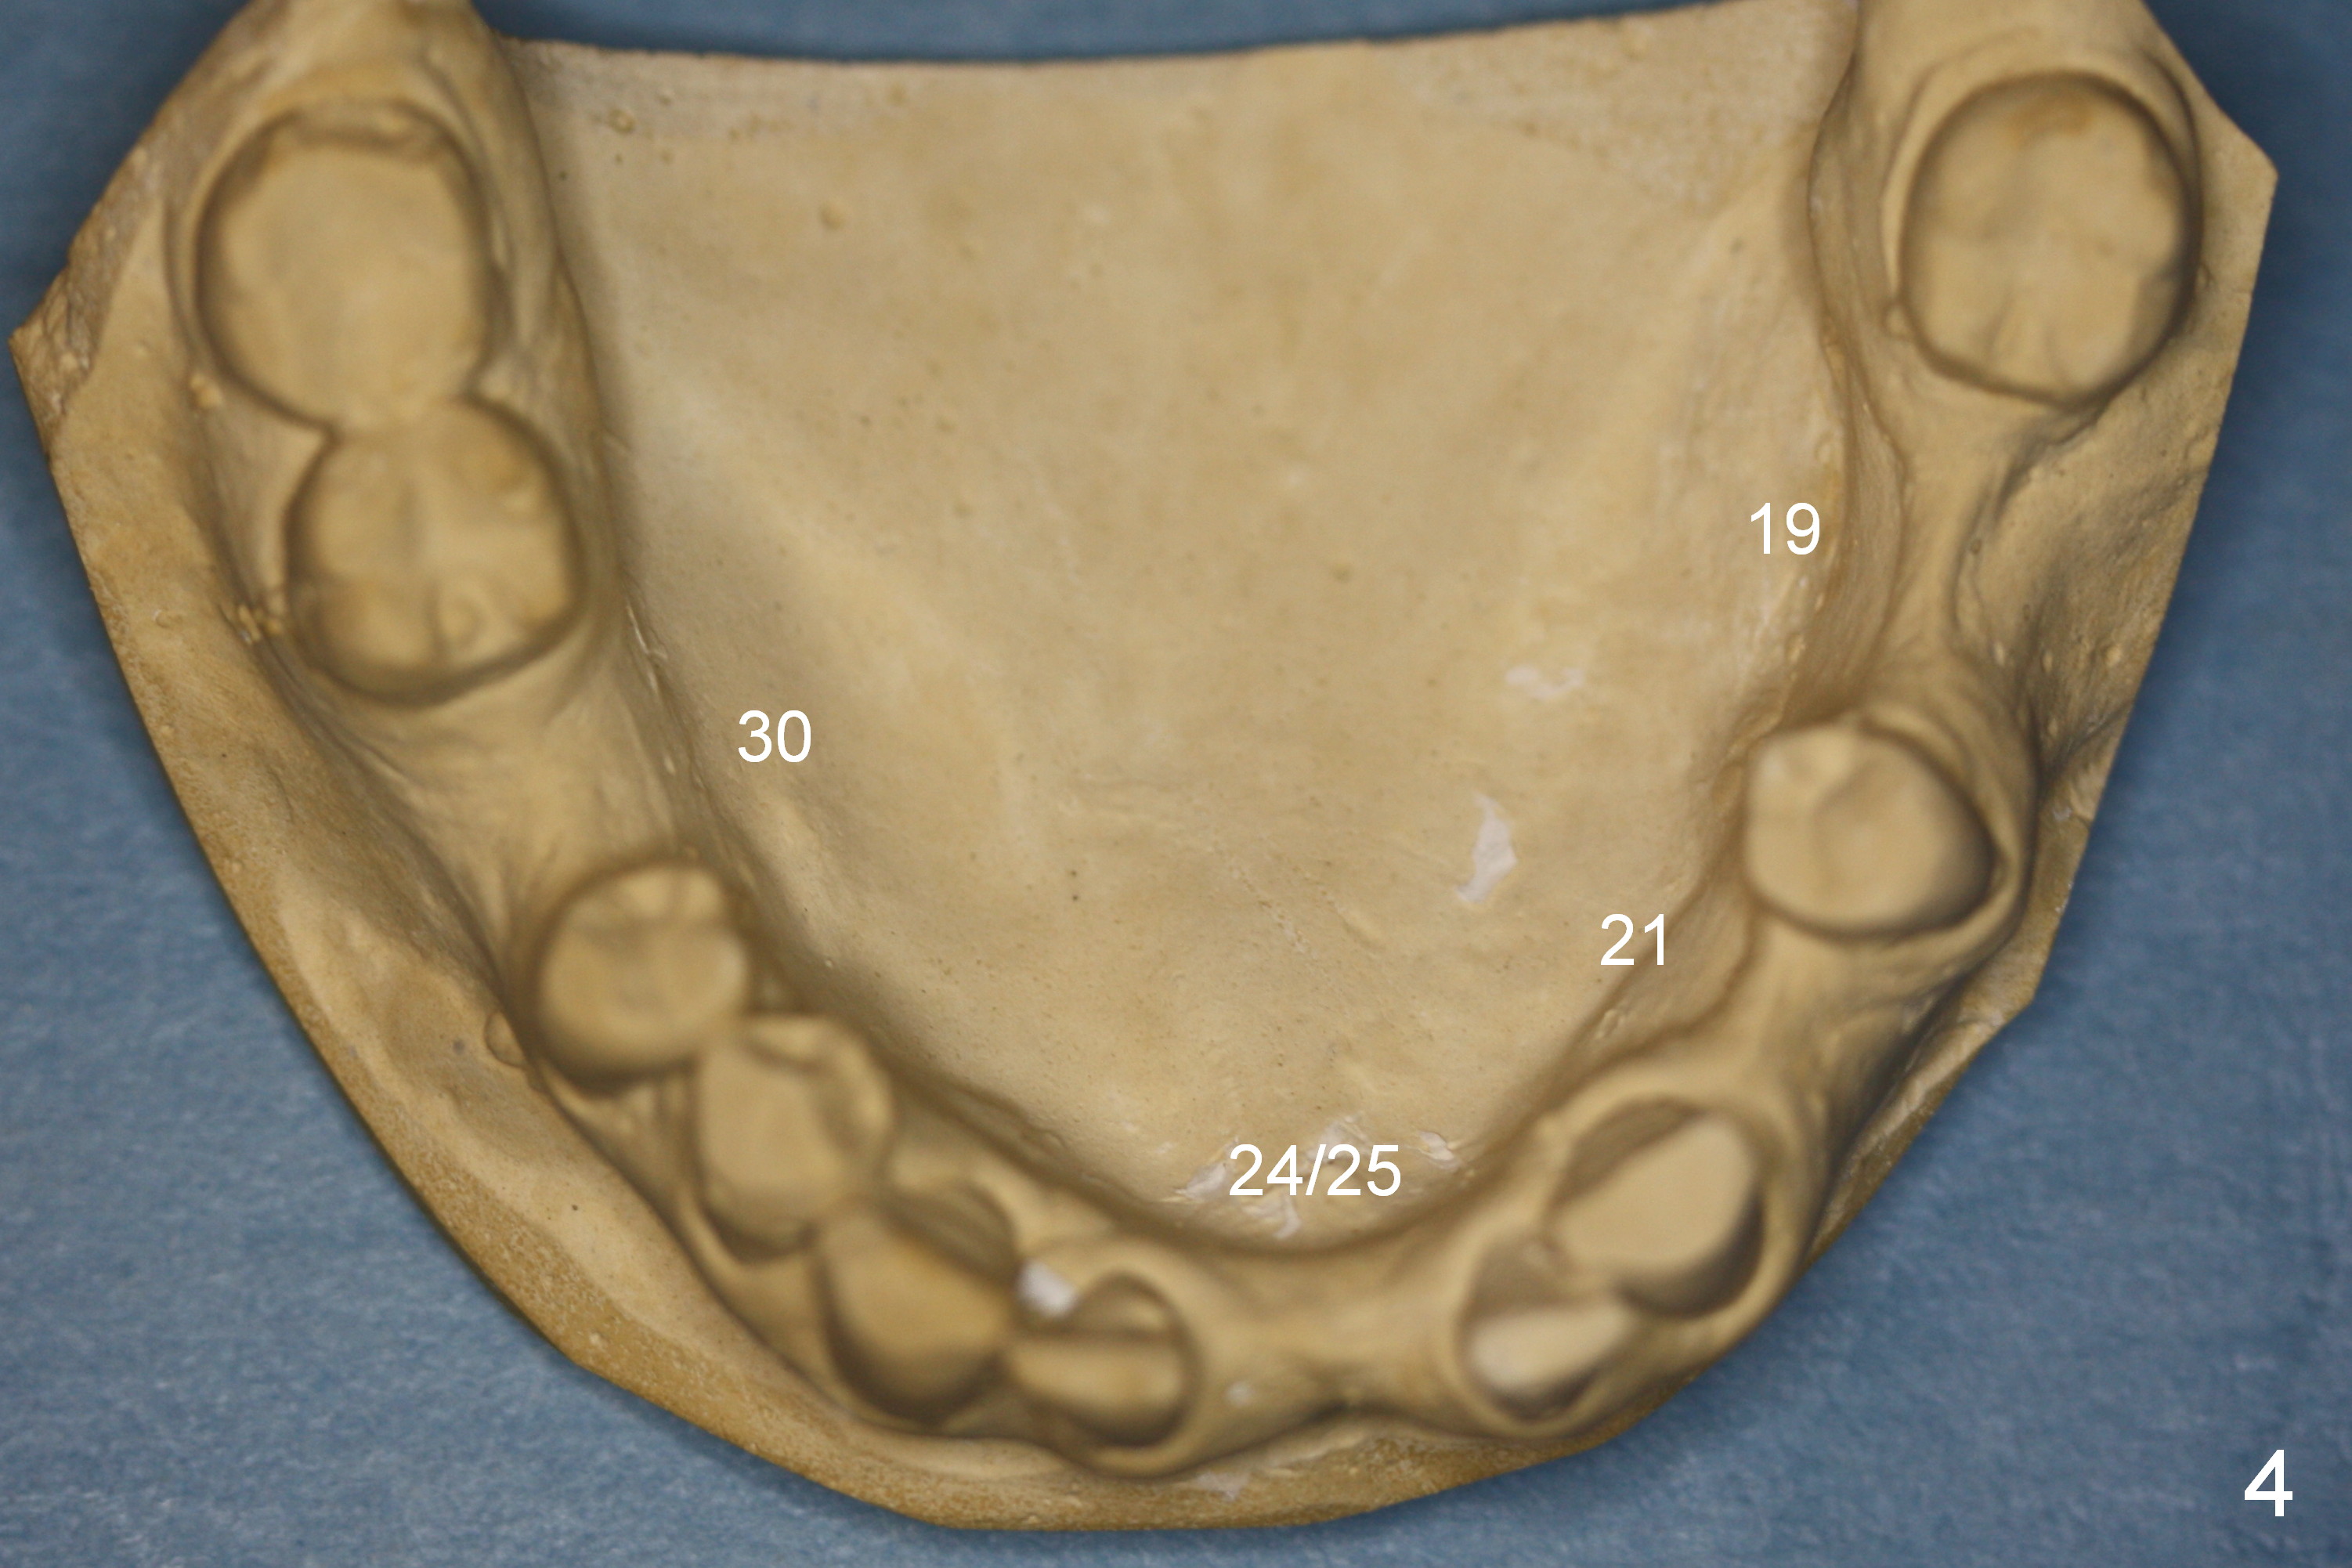

The buccolingual width at the sites of #19 and 21 appears narrow (Fig.4). On the other hand, the mesiodistal width at #19 seems to be wider than one molar and narrower than two (Fig.4-6). If CBCT and/or surgery confirms that the buccolingual bony width is narrow, two small diameter implants will be placed with restoration of two bicuspids.